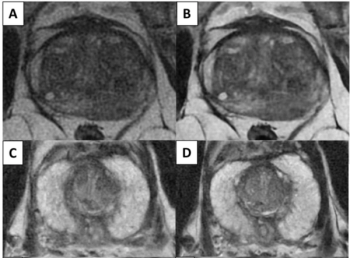

In a study involving over 1,000 visible prostate lesions on biparametric MRI, a deep learning algorithm detected 96 percent of clinically significant prostate cancer (csPCa) in comparison to a 98 percent detection rate for an expert genitourinary radiologist.

MRI Study Suggests Deep Learning Model Offers Equivalent Detection of csPCa as Experienced Radiologists